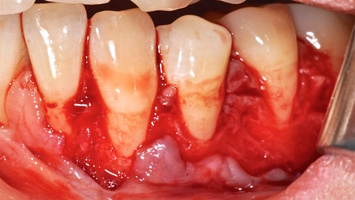

7. Этапы хирургического лечения рецессий десны на верхней челюсти

Второй сегмент был прооперирован через 4 месяца после операций на нижней челюсти, область операции включила в себя зубы от 2.1 до 2.6.

В области 2.3 зуба глубина рецессии составила 6 мм (2-й класс по Миллеру), кератинизированная десна отсутствует, толщина слизистой — 0,7 мм. Это показание к применению аутотрансплантата(свободного десневого деэпителизированного трансплантата) именно в области 2.3 зуба. Донорская зона позволила сделать забор аутотрансплантата размером 15 мм, которого хватило на общую ширину рецессий двух зубов: 2.3 и 2.4.

При устранении рецессий десны коронально-смещенным лоскутом по De Sanctis M. и Zucchelli G. в остальных участках был использован пластический материал аллогенного происхождения — ТМО (dura mater).

Хирургический протокол операции соответствовал технике коронально-ротированного смещения, пласти- ческий материал и аутотрансплантат были полностью перекрыты слизисто-надкостничным лоскутом и зафиксированы швами. Обработка поверхностей корней зубов проводилась аналогично.

Первый сегмент был прооперирован через 2,5 месяца после операции во втором сегменте.

В области 1.3 и 1.2 зубов выявлены рецессии десны глубиной 6 мм 2-го класса, полное отсутствие прикре- пленной десны, толщина ее составила 0,6 мм. Зона хирургического устранения рецессий от 1.6 до 1.1 зубов.

Протокол операции коронально-ротированного лоскута по методике M. De Sanctis и G. Zucchelli: дизайн разрезов с измерением глубины рецессий, отслаивание слизисто-надкостничного лоскута и его мобилизация.

Деэпителизация анатомических сосочков, обработка поверхностей корней зубов, фиксация свободного десневого аутотрансплантата и пластического материала ТМО (dura mater) швами, с полным перекрытием слизисто-надкостничным лоскутом, фиксация швами слизисто-надкостничного лоскута узловыми одиночными швами в области установки аутотрансплантата и ТМО (dura mater), двойными обвивными для слизисто-надкостничного лоскута, и крестообразными прижимающими горизонтальными швами для фиксации слизисто-надкостничного лоскута в новом положении. Обработка поверхностей корней зубов проводилась аналогично.